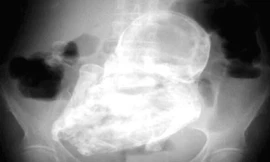

Nhập viện vì bị ngã, một cụ bà 92 tuổi ở Chile khiến các bác sĩ kinh ngạc khi phát hiện một bào thai hóa đá nặng gần 2 kg nằm trong khoang bụng của bà.